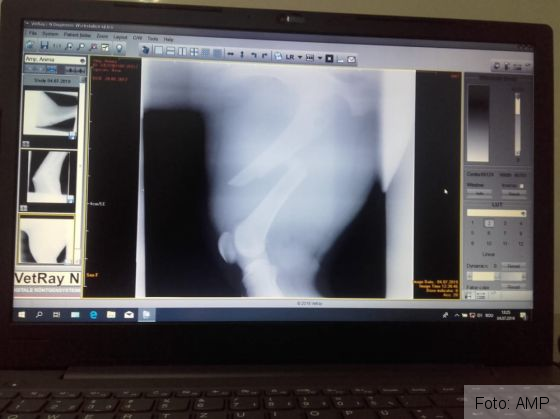

„Astăzi i-a fost făcută o radiografie care a confirmat temerile medicilor veterinari colaboratori ai AMP: fractură de femur cu deplasare la piciorul drept, spate. Radiografia a scos însă la iveală și o problemă mai veche, la piciorul drept-față al ursoaicei: o luxație de articulație, cu posibilă ruptură de ligamente. Rezultatele vor ajunge astăzi în Germania, la medicul veterinar specialist care sperăm să o opereze pe tânăra ursoaică. Acum așteptăm cu toții costurile estimative ale intervenției, dar și o dată aproximativă în care poate fi efectuată operația”, a precizat Paula Ciotloș, reprezentantă AMP. Persoanele care vor să-i ajute pe cei de la AMP s-o salveze pe Anima pot găsi detalii AICI!